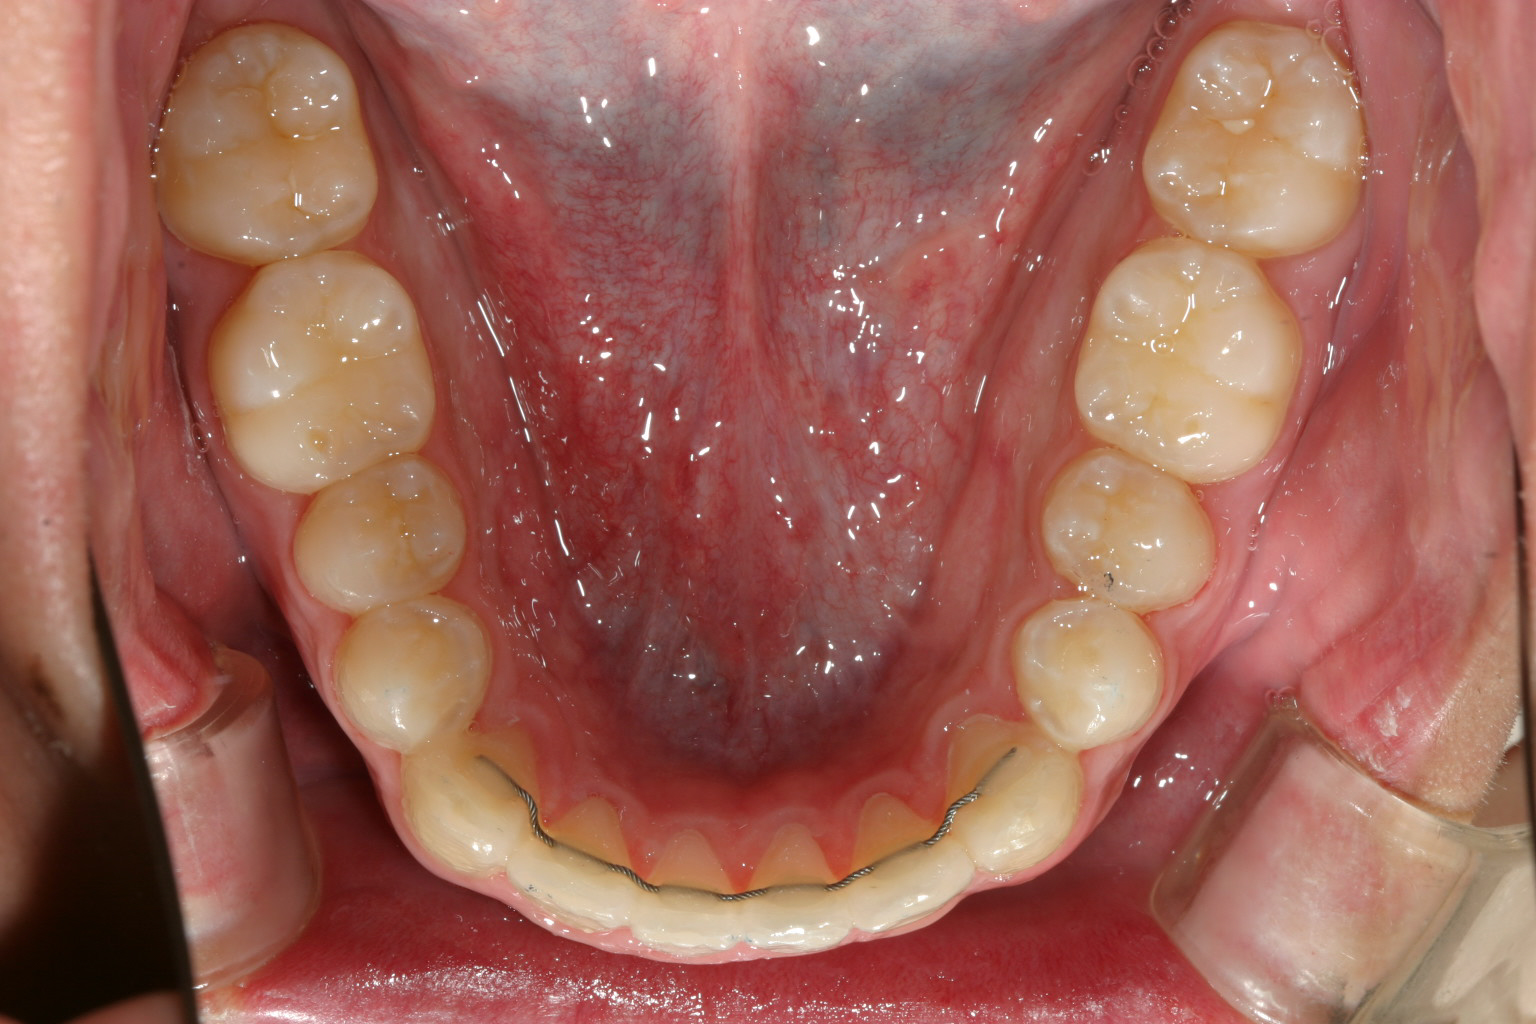

下顎も綺麗に改善しました。

下顎もアーチが狭い為叢生になっています。